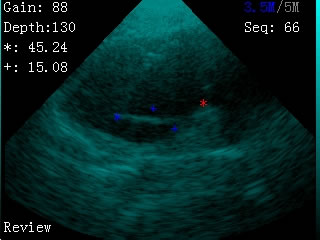

我司最新推出的V2型腕式B超,主机重量仅140克,看成目前全世界最轻的B超。

V2型腕式扇扫B超由主机、探头、外置电池、手握式键盘组成,重量只有140g(不含探头和电池)堪称全世界最轻的B超。

·具有伪彩显示功能

-扫描方式:机械扇扫

-探头频率:3.5MHz/5MHz双频率可变频探头

-扫描深度:≥180mm,70、110、130、150、192mm五档可调

-显示模式:B

-测量内容:距离